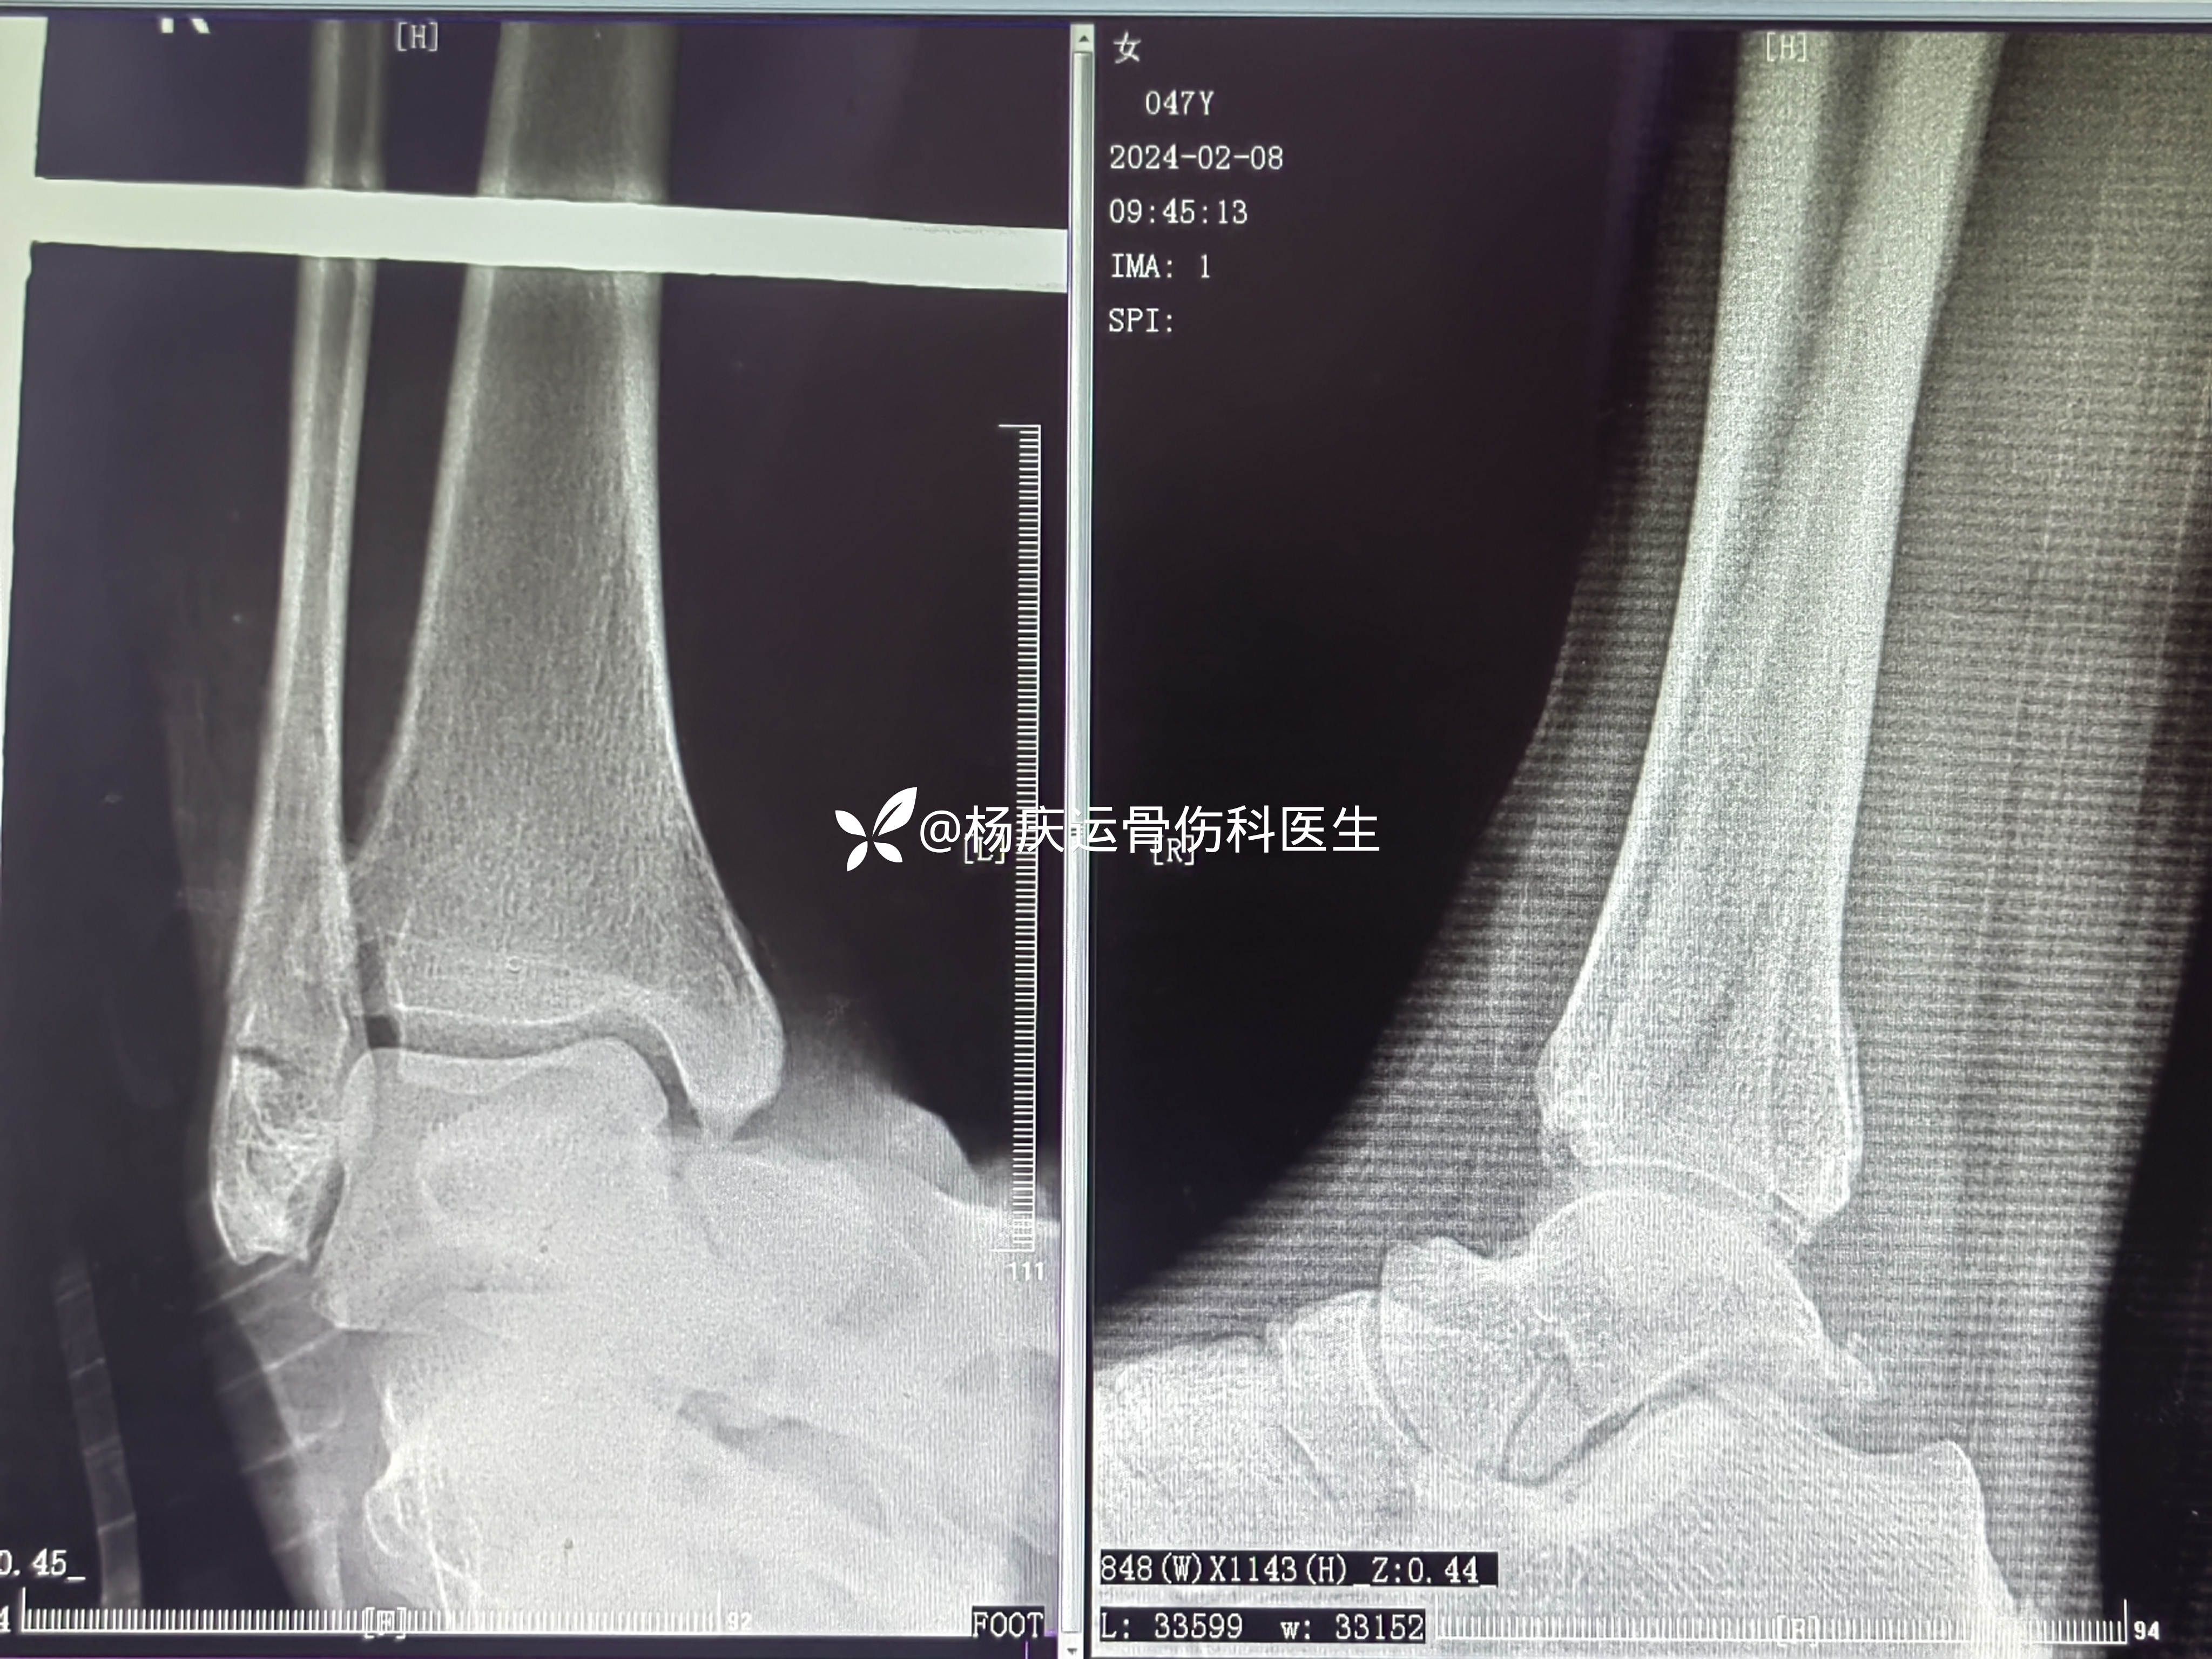

患者宋女士,47岁,右踝扭伤肿痛活动受限2小时于2024-1-30来诊。

初步诊断:右踝关节骨折

治疗方案:闭合复位夹板纸壳靴外固定治疗

复位后